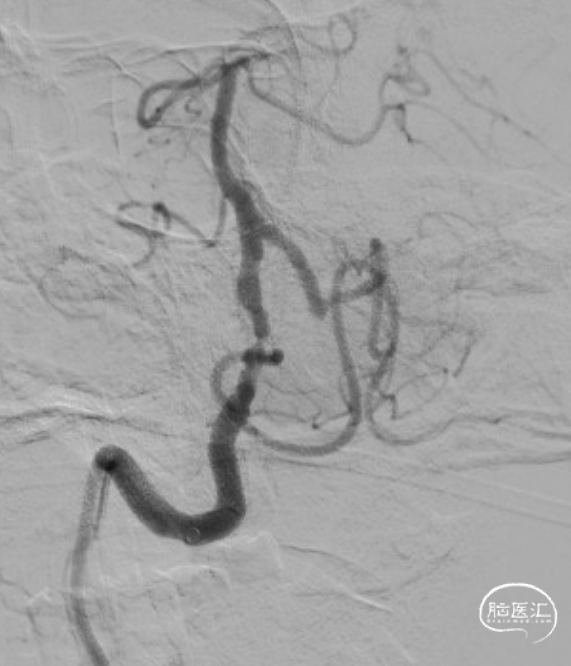

赛诺NOVA®颅内药物洗脱支架 2.75*12mm输送至病变段。

10atm压力释放赛诺NOVA®颅内药物洗脱支架。